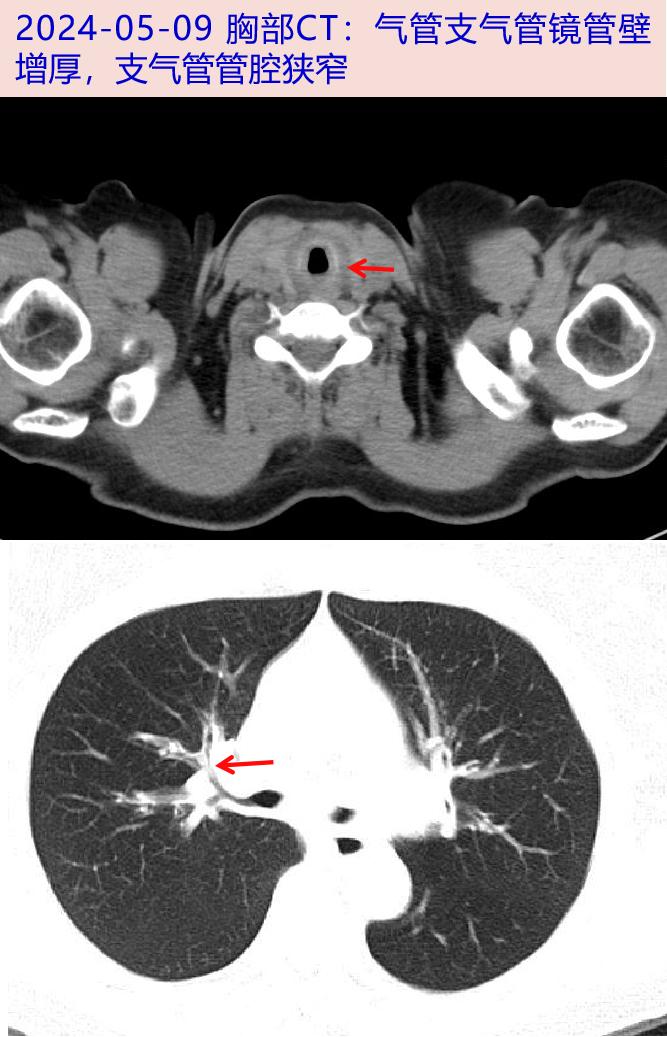

2023-10 咳嗽加剧,咳白色泡沫痰,2023-11-03当地胸部CT:气管壁稍增厚,考虑淀粉样变性,两肺多发微小结节。

2024-03 出现间断发热,Tmax 39℃,咳嗽加重。2024-03-09 当地胸部CT:肺纹理增多,气管壁增厚,考虑为淀粉样变,两肺微小结节。

病史特点:患者中年女性,慢性病程,主要表现为咳嗽咳痰气促、发热,体检有哮鸣音;胸部CT示气管支气管管壁增厚;中性粒细胞百分比、ERS及CRP升高;氟喹诺酮类抗感染效果不佳,疾病诊断和鉴别诊断考虑如下:

支气管哮喘:是呼吸系统常见病、多发病,由多种细胞和细胞组分参与的气道慢性炎症性疾病。其病因与发病机理尚未完全清楚。临床主要表现为反复发作的咳嗽、咯痰、喘息、胸闷、呼吸困难等,典型的表现是发作性伴有哮鸣音呼气性呼吸困难。支气管舒张试验、激发试验阳性。患者哮喘史、过敏性鼻炎病史,无长期反复发作性喘鸣病史,目前支持依据不足。支气管哮喘CT通常阴性,无明显肺内病灶及实质病变,该患者CT示气管支气管壁增厚,不符合支气管哮喘的影像学表现。

淀粉样变:淀粉样变是蛋白质以异常的纤维组织形式沉积于细胞外组织而引起的少见病。累及呼吸道者,可表现出干咳的症状,影像学上可见到气管支气管壁弥漫均一增厚。若淀粉样变在气管支气管内引起气道部分阻塞,就可出现哮鸣音、呼吸困难及阻塞性肺炎症状。可完善支气管镜下取气道内组织行病理学检查进一步排查。

复发性多软骨炎:累及肺部时可出现咳嗽、气喘、发热等症状,该患者入院后胸部CT示气管支气管管壁明显增厚,需警惕气管软骨炎症可能;补充查体,未见鞍鼻、耳廓红肿畸形等,入院后可行PET/CT评估全身软骨炎症、行支气管镜检查等明确。

患者中年女性,慢性起病;主要表现为发热、咳嗽、咳痰,伴有气促等非特异性症状;CRP、ESR明显升高,铁蛋白升高,自身抗体阴性、病原学检测阴性,胸部CT:支气管壁增厚;支气管镜下可见气管及叶、段支气管壁粘膜肿胀,病理活检未见恶性细胞。PET/CT示累及全身多处软骨(气管、甲状软骨、环状软骨、双侧多处肋软骨)可能;糖皮质激素治疗后体温平,咳嗽咳痰气促好转,炎症标志物下降;故诊断成立。

RP累及气道时,CT影像表现为气道壁增厚、钙化,气道软化、狭窄等;气管镜下见气道黏膜肿胀、软骨环消失等征象,导致气管狭窄、塌陷等。但上述征象均无特异性。而PET/CT对于软骨炎有独特的FDG摄取表现,故在早期诊断中具有重要意义,还可判断疾病活动度和累及范围,如对高代谢灶进行活检可提高阳性检出率。本例患者胸部CT影像及气管病理为非典型RP,但PET/CT多部位软骨FDG摄取增高符合典型软骨炎症表现,进一步协助RP诊断。此外,血沉、CRP在本病活动期可明显升高。本例患者表现为血沉增快(80mm/h),CRP大于100mg/L,而毒血症状不重,抗感染治疗无效,此时需注意排查风湿免疫系统疾病。血沉及CRP在风湿免疫系统疾病中不仅会随病情的恶化或好转而升高或降低,且与疾病的严重程度、预后密切相关,也是达标治疗的重要指标。中山感染病科已诊断此病近10例,本病虽不是感染病,但容易误诊为呼吸道感染,给予抗感染治疗。感染病科医生必须学习此疾病,避免误诊及滥用抗生素。如误诊可导致管腔狭窄及塌陷,不利于疾病的恢复,可导致患者反复发生肺炎。